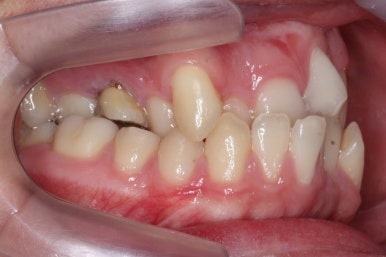

얼굴모습과 인 안의 모습을 종합했을 때, 치아교정만으로 치료를 하기로 했습니다.

만약 위턱뼈의 저성장 양상이 심했다면 악교정수술(흔히 말하는 양악수술)이 필요하게 됩니다.

좁아져 있는 위턱뼈를 가로로 넓혀주기 위해서 악궁확장장치를 사용했습니다.

윗니는 선천결손으로 치아가 2개가 모자랐고 앞니도 거꾸로 물리는 상황이여서 아랫니도 균형있게 2개를 추가로 더 뽑았습니다.